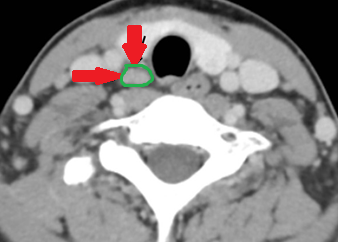

Contrast-enhanced CT demonstrates soft-tissue lesion in left carotid sheath (Courtesy Dr. V. Penopoulos)

Neck SPECT/CT. Green arrow — Ectopic (within the sheath) parathyroid adenoma. Red arrow — Right common carotid artery (Courtesy Dr. V. Penopoulos)